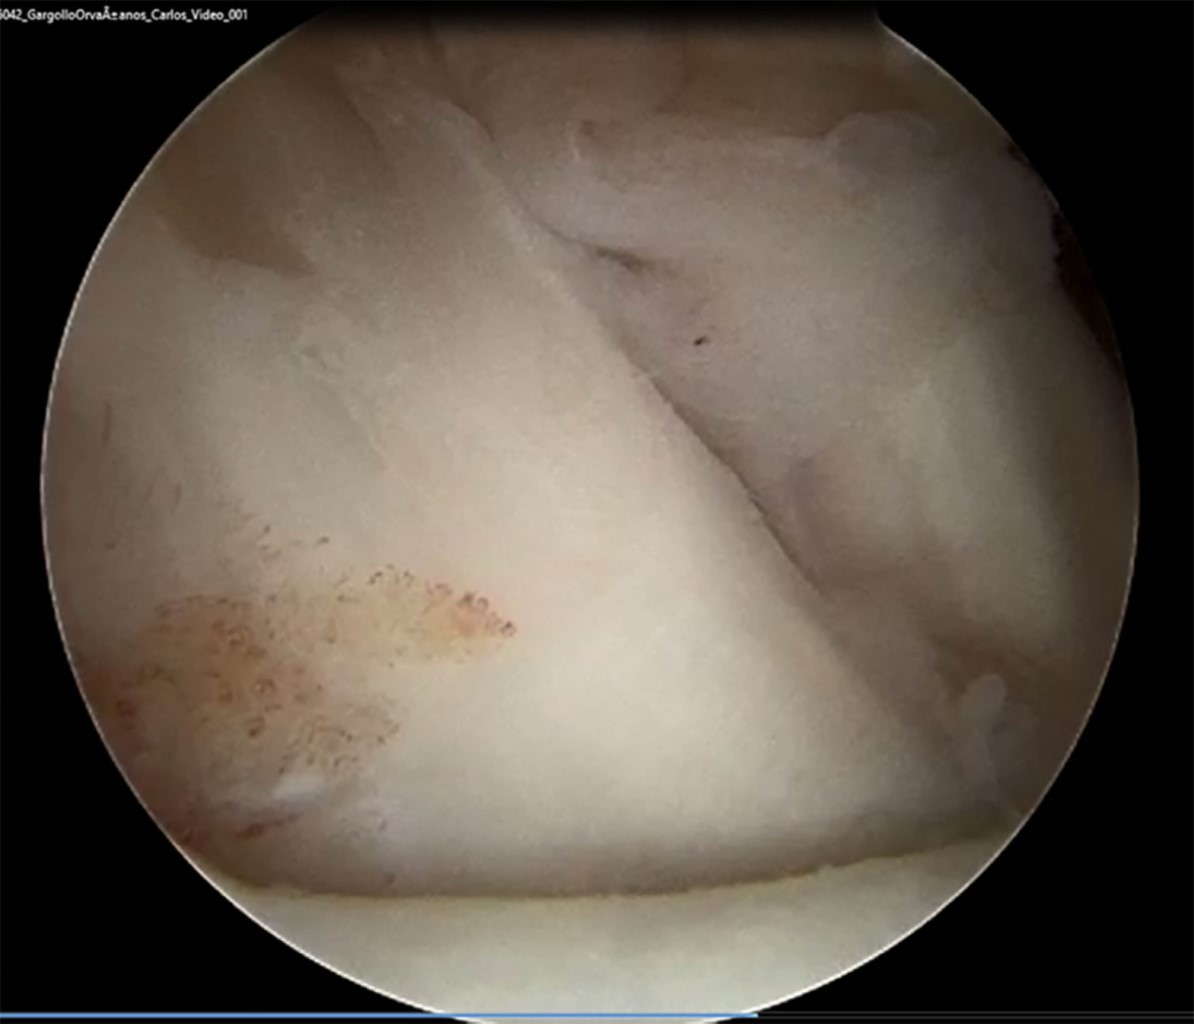

Se incluyeron a todos los pacientes que cumplieron con los criterios de inclusión de los que se tiene registro para este estudio, aunque la muestra fue pequeña. Asimismo, se decidió agotar todas las opciones terapéuticas no invasivas antes de pasar a la reparación quirúrgica mediante artroscopía de muñeca, por lo que existe una mayor ventana de tiempo entre la resonancia magnética y la artroscopía de muñeca, pudiendo dar espacio a una mayor cantidad de lesiones y/o gravedad de estas. En la Figura 2 se observa lesión del ligamento escafosemilunar observada mediante resonancia magnética y artrosocopia de muñeca en el mismo paciente. En la Figura 3 se observa lesión del fibrocartílago triangular Palmer 1D. Y en la Figura 4 se observa lesión del ligamento radioescafogrande.

Figura 3